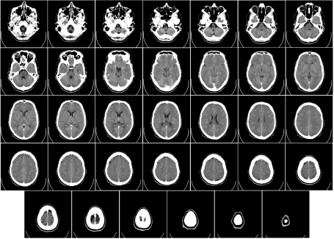

Image Diagnosis

A picture is worth a thousand words, and in the fields of medicine and product development, non-intrusive diagnostic images such as X-rays, CT scans, and MRIs can be the difference between life and death. Our team has supported numerous medical professionals and industrial experts in resolving critical issues, aiding both human patients and products alike.

We work with a large group of medical professionals to analyze and curate medical images, including ultrasound, x-ray CT, and MRI.